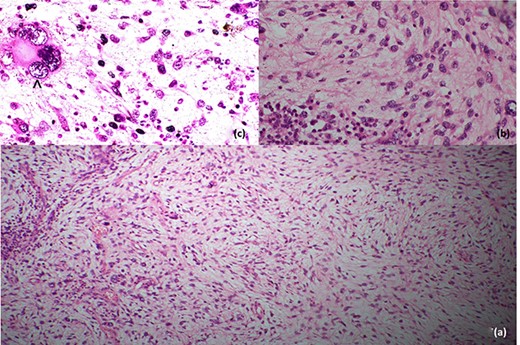

Histopathological evaluation revealed a 24 × 21 × 15 cm tumour weighing 2.645 kg (Fig. 4b) with fibrotic, solid and cystic degenerative changes without capsular infiltration or vascular invasion. There were diffuse sheets of storiform-spindle cells with variable cellularity, bizarre multilobulated and bare nuclei, eosinophilic inclusions and high mitotic activity (Fig. 5). Foci of bony metaplasia were noted in the hard area of the capsule. No adrenal tissues were identified in the entire specimen. The tumour stained immunohistochemically positive for CD68, CD99, CD34 (40%), desmin (20%) and smooth muscle actin (SMA) (10%) but was negative for Pan-CK, S100, Melan A, epithelial membrane antigen (EMA), human melanoma black 45 (HMB45), CD117, B cell lymphoma 2, chromogranin and synaptophysin (Fig. 6). No metastases were identified on screening. We referred the patient to oncology for evaluation, but they did not recommend chemotherapy, and there have been no recurrences through the 18-month post-operative period.

Histopathological features; (a) low-power image showing spindle cells in pleomorphic-storiform pattern, (b) high-power image showing spindle cells with bizarre multilobulated nuclei and (c) very high-power image depicting a nucleus in a spindle cell; the black arrowhead in (c) shows high mitotic activity in a spindle cell.